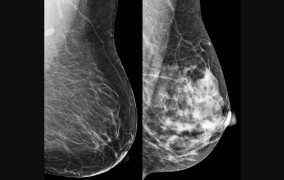

Descoberta aumentou de 13 para 90 o número de variações conhecidas da proteína HER2, alvo de medicamentos avançados contra a doença; diversidade pode explicar resistência a terapias